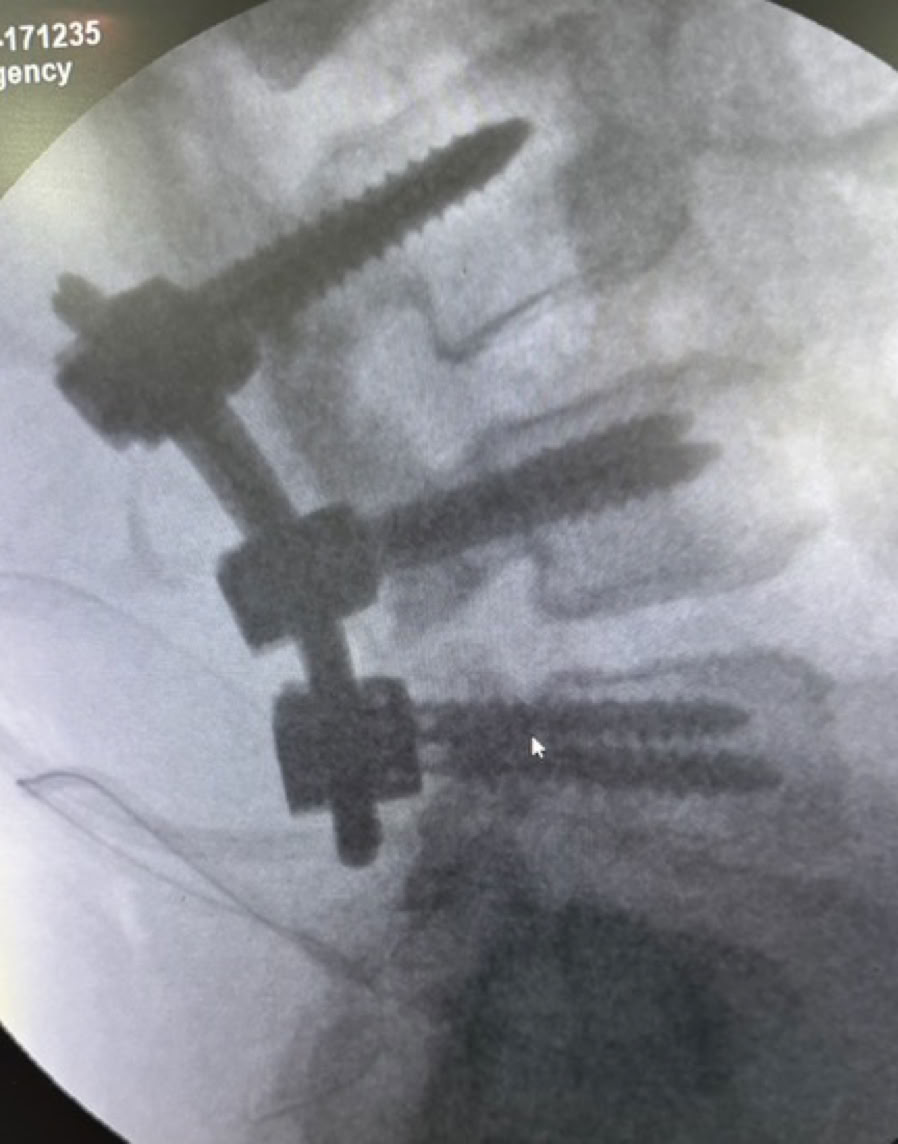

Nos encontramos dos casos de rodillas flotantes que pudimos resolver y casos de retardo de consolidación e infecciones de intervenciones previas. Igualmente las osteomielitis hematógenas y las sécales de la diabetes ocupa gran parte de la actividad de consultas de sala de curas y de las sesiones quirúrgicas.

A partir del lunes y tras la oración de bienvenida al inicio de la jornada en la que nos fuimos presentando todos los componentes de la expedición, las tareas asignadas se fueron distribuyendo entre la consulta, las dos salas de Curas y los dos quirófanos, que además se han mantenido activos todos los días de la semana en turnos de mañana y tarde con cirugías complejas en ambos. Esto nos ha permitido por ejemplo abordar principalmente enclavados de fémures y tibias y también casos de luxaciones inveteradas de hombro y de tobillo.

Como en expediciones anteriores, las complicaciones de cirugías previas en otros centros, la demora de los tratamientos por el empleo de la medicina tradicional (masajes) mencionada antes, y la elevada tasa de infecciones tanto hematógenas como secundarias a diabetes mal controlada o sin tratamiento, han ocupado gran parte de nuestro trabajo.